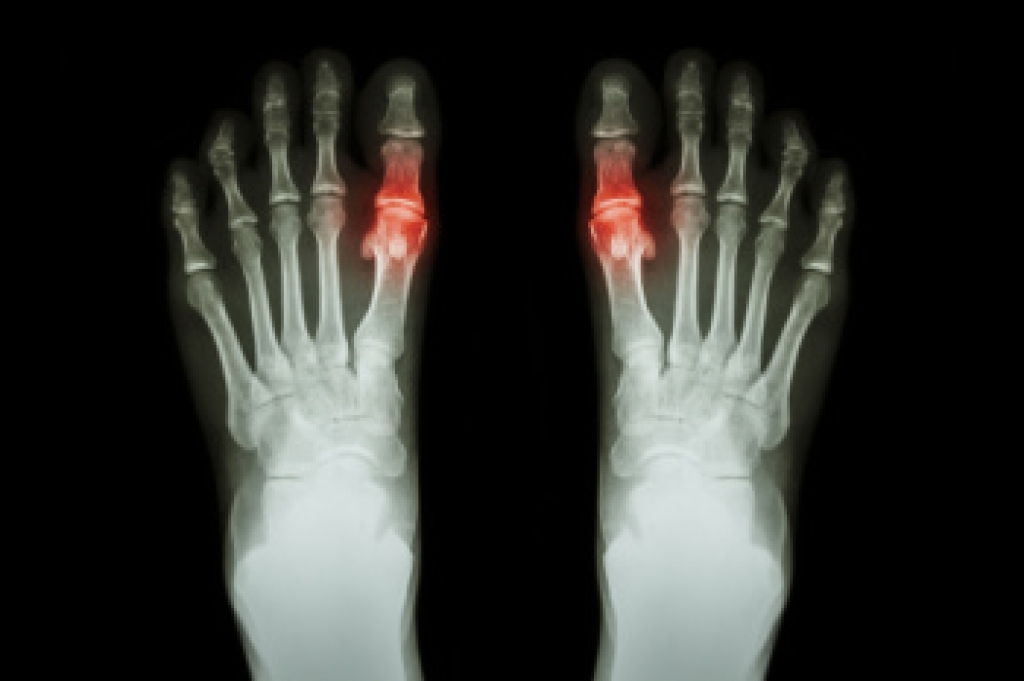

Foot pain is a very broad condition that could be caused by one or more ailments. The most common include:

- Bunions

- Arthritis (such as Gout, Rheumatoid, and Osteoarthritis)

To figure out the cause of foot pain, podiatrists utilize several different methods. This can range from simple visual inspections and sensation tests to X-rays and MRI scans. Prior medical history, family medical history, and any recent physical traumatic events will all be taken into consideration for a proper diagnosis.